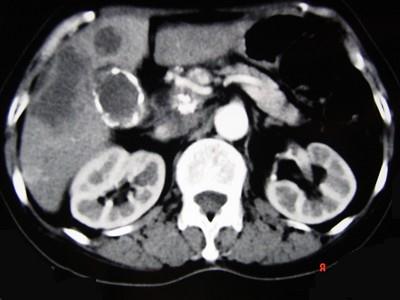

问题 女,66岁,右上腹痛,发热伴有黄疸两月余,消瘦、纳差,影像检查如图,最可能的诊断是 ( )

选项 A、肝内胆管细胞癌 B、胆囊癌及原发性肝癌 C、胆囊结石及肝血管瘤 D、胆囊癌肝转移 E、胆囊结石及脂肪肝

答案 D